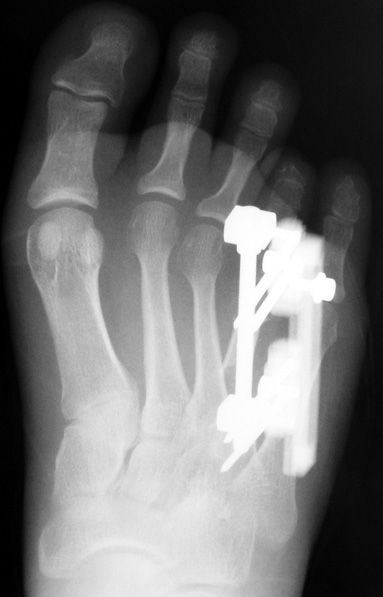

Doğuştan metakarp ve metatars kısalıklarının redavisi için pek çok teknik tanımlanmakla birlikte en çok akut uzatma sonrası kemik uçlarına greft konması ve distraksiyon osteogenezi (kallotasis) kullanılmaktadır. 1 cm.den daha fazla uzatma gereken olgularda kallotasis yöntemi önerilmektedir. Kliniğimizde de metatars ve metakarp uzatma için unilateral eksternal fiksatör ve sirküler eksternal fiksatör yardımıyla distraksiyon osteogenezi yöntemi tercih edilmektedir.